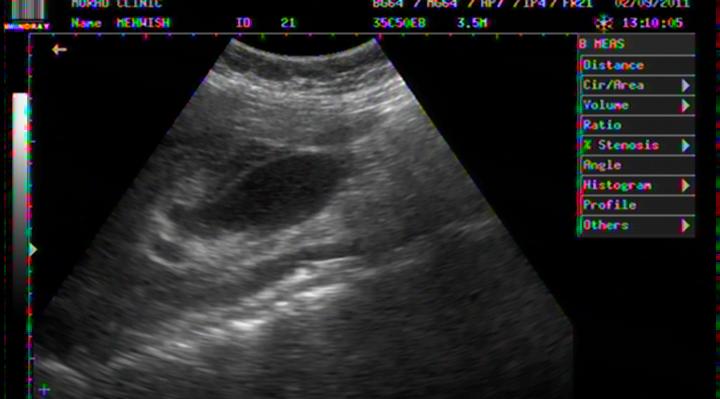

PELVIC ASCITES IN DHF

EVERY DHF PATIENT MUST HAVE EVIDENCE OF PLASMA LEAKAGE AND THROMBOCYTOPENIA.